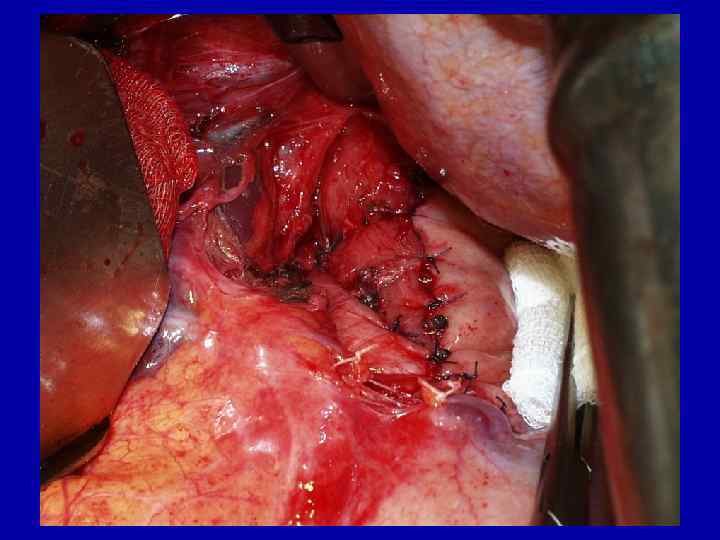

Больной К. , 54 л. Ds: Рак средней трети пищевода 05. 02. 2003 – Экстирпация пищевода из трех доступов с одномоментной пластикой желудочной трубкой

Больной М. , 69 л. Ds: эпидермоидный рак средней трети пищевода 04. 09. 03 - трансхиатальная экстирпация грудного отдела пищевода с одномоментной пластикой изоперистальтической желудочной трубкой, стандартная торакоабдоминальная лимфаденэктомия

Больной Б. 64 г. 30. 03. 2005 – экстирпация пищевода с пластикой желудочной трубкой.